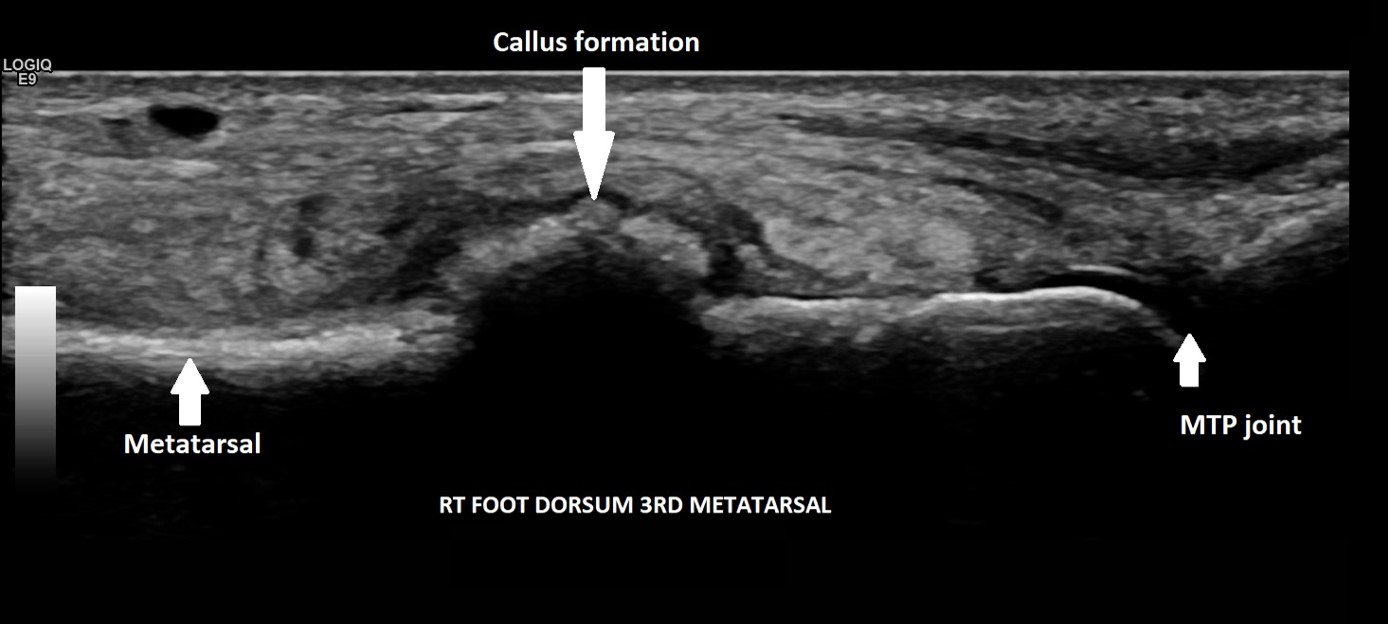

A 29-year-old female, presented with pain and a lump on the dorsum of her right foot. She was training for a 10km run and had been struggling with running over a 6-week period. No history of trauma or erythema to the skin. The clinical suspicion was a ganglion, and the patient was referred for an ultrasound scan for further assessment.

On the dorsum of the foot, ultrasound demonstrated marked cortical irregularity and callus formation around the third metatarsal shaft accounting for the palpable ‘lump’ with surrounding soft tissue swelling (Figure 1). On power Doppler, there was marked peripheral vascularity in the surrounding soft tissues (Figure 2). Incidentally, there was also cortical irregularity and callus formation around the second metatarsal shaft although the patient was not particularly tender here whilst scanning (Figure 3). The cortical irregularity in the second metatarsal shaft was minimal when compared to the third metatarsal and there was no neovascularisation on power Doppler indicating this was an older/mature injury.

Ultrasound appearances in keeping with acute and chronic stress fractures. A radiograph confirmed old and new callus formation (Figure 4). Conservative treatment comprised rest and analgesia. Surgery is generally reserved for stress fractures that do not heal.